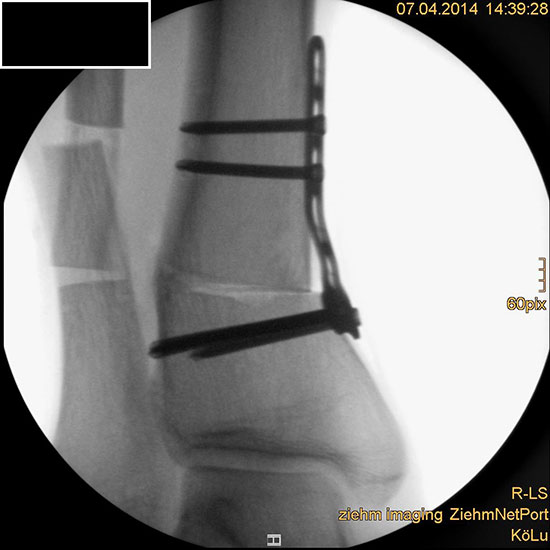

Wir benutzen zur Osteosynthese 3,5 mm LCP T-Platten. In der intraoperativen Röntgenkontrolle kann im seitlichen Bild die Zentrierung des Talus überprüft werden, und ggf. durch eine milde extendierende oder flektierende Korrekturkomponente verbessert werden 18. Eine begleitende Deformität der Fibula korrigieren wir üblicherweise mit einer z-förmigen Osteotomie die wir mit einem 1/3 Rohrplättchen sowie einer Zugschraube sichern 18.